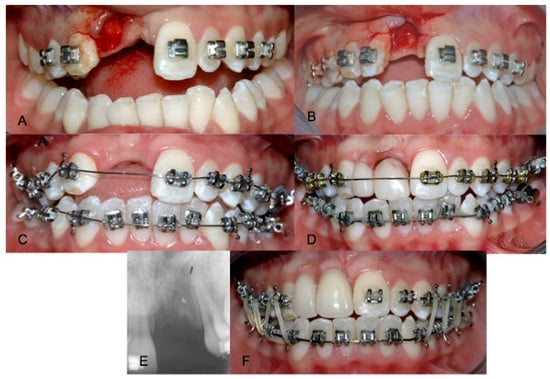

Treatment was conducted in accordance with good clinical practice (GCP) established in the Declaration of Helsinki, and the treatment procedure, risks and benefits were completely explained to the parents and then written informed consent was obtained. After splint removal, the mobility of both teeth (degree 2 on the Miller scale) was evaluated and teeth #11 and #12 were extracted.

Orthodontic treatment was then performed on both arches to maintain spaces and harmonize the occlusion. A removable partial denture was delivered in order to restore the edentulous area (Figure 2).

Four months later, intraoral and extraoral photographs, the impression and the facial arch for mounting the articulator were taken. Additionally, radiographic exams were required. After clinical and oral evaluations, two mini-implants were planned for the edentulous space via radiographic and stone casts evaluation. Under computerized local anesthesia, a full-thickness paramarginal incision was made. Bone was surgically exposed, and the surgical guide was positioned. Two 2.5 mm diameter by 13 mm length mini-implants (Sweden Martina, Italy) of grade 5 titanium alloy with a sandblasted surface were placed in areas #11 and #12 using a dynamometric torque wrench. The mini-implants were positioned through the use of a surgical guide. After the flap was primary closed around the prosthetic attachments, the removable prosthesis was repositioned, and radiographic verification was performed (Figure 3).

Figure 2. (A) Extraction of 12, (B) extraction of 11, (C) start of orthodontic therapy, (D) removable prosthesis placement, (E) periapical X-ray after two months and (F) orthodontic treatment after 4 months.